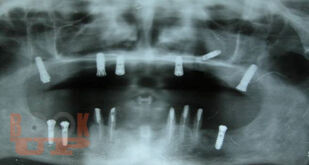

В учебном пособии рассматриваются вопросы клинико-рентгенологической диагностики хирургических осложнений дентальной имплантации, возникающие в интраоперационном и раннем послеоперационном периодах. Разделы пособия содержат клинические примеры осложнений, возникающих на хирургическом этапе имплантологического лечения больных. В отдельной главе, посвященной социологическому исследованию, приведены данные анкетирования врачей-стоматологов по проблемам имплантологического лечения, которые позволяют выявить наиболее острые проблемы, стоящие перед имплантологами, в том числе, пробелы в послевузовском образовании. Пособие иллюстрировано цветными фотографиями, облегчающими восприятие излагаемого материала.